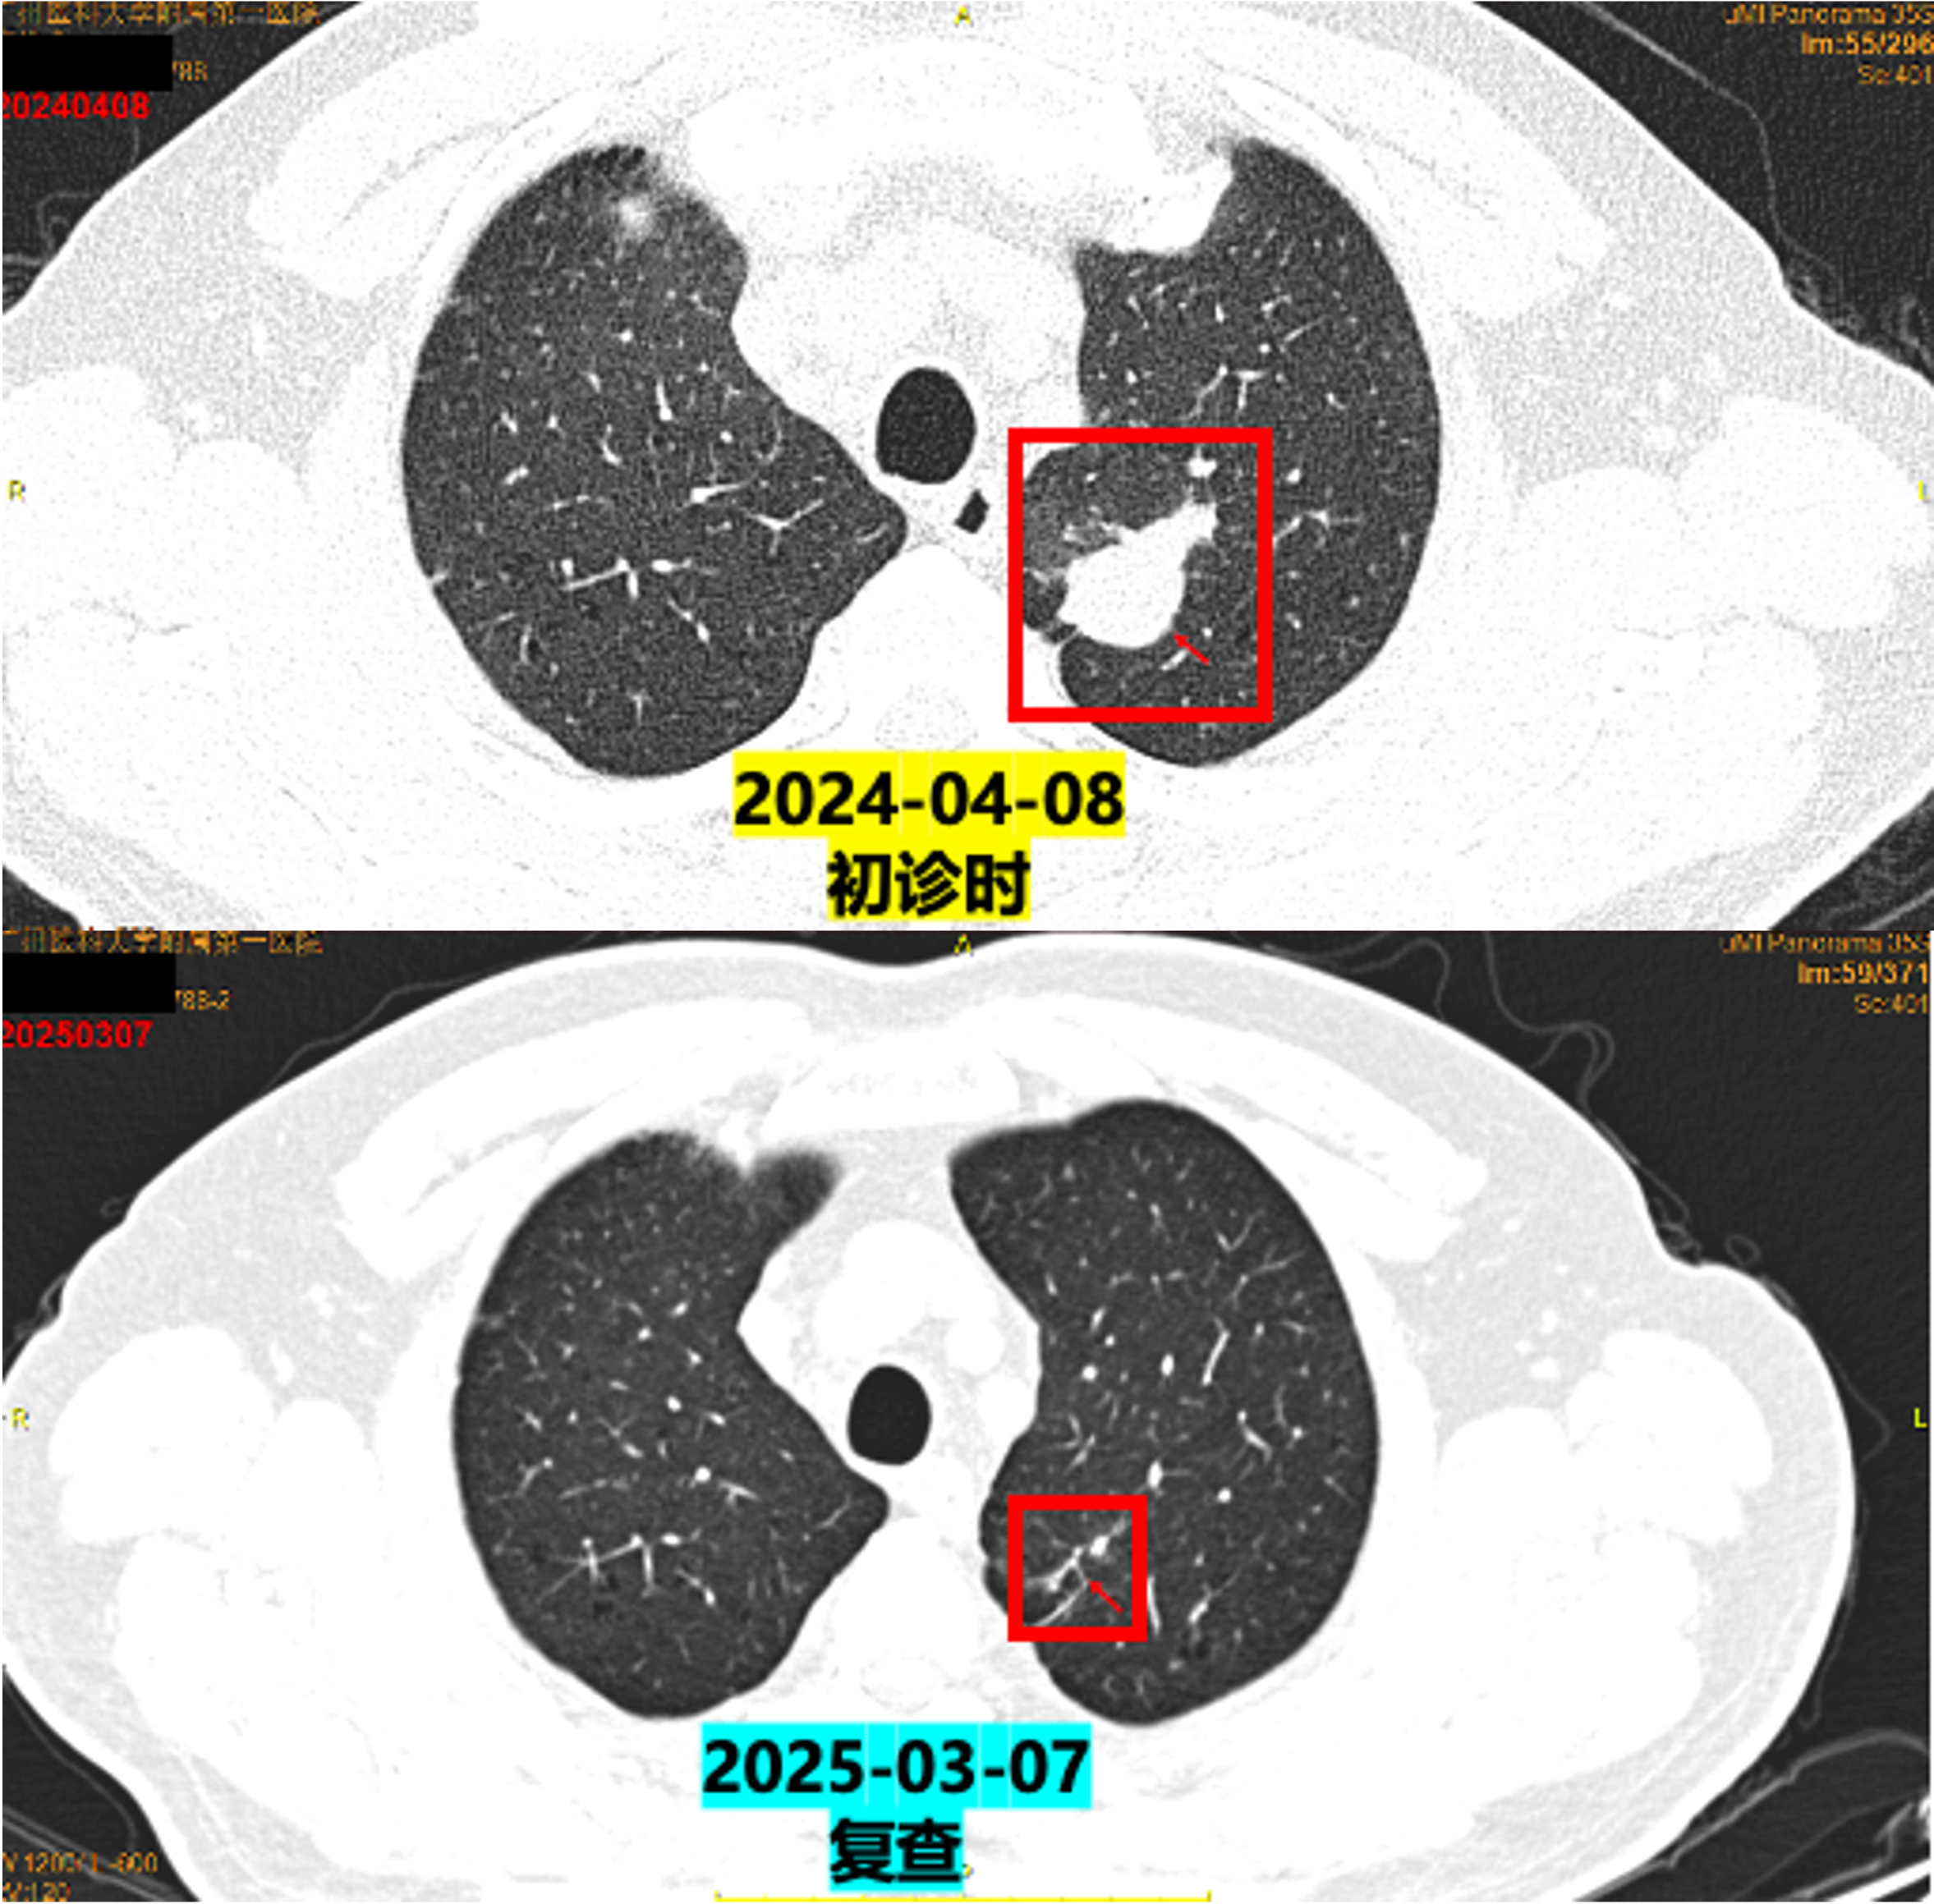

临床随访影像对比

2024-04-08(初诊)vs 2025-03-07(复查)PET/CT:

左肺上叶尖后段实性结节体积缩小(较大约0.8×0.8×1.1cm vs 原1.9×1.8×2.4cm);

左肺门、纵隔多发淋巴结转移瘤体积缩小;

左侧肾上腺结合部增粗程度减轻。

在2025年3月7日复查petCT后,建议患者行原发病灶或者肺门、纵隔淋巴结的放疗,但是患者家属自觉目前治疗疗效理想,患者体能状态良好,暂不愿意行放疗。

疗效评估:PR(部分缓解)。

本例患者为MET扩增晚期肺腺癌,一线使用MET抑制剂特泊替尼后疾病快速进展,是典型的原发耐药,预后较差。更换为舒格利单抗联合培美曲塞和卡铂的方案后,患者获得了长达1年以上的持续部分缓解(PR),这充分展示了免疫联合化疗在这一挑战性人群中的价值。